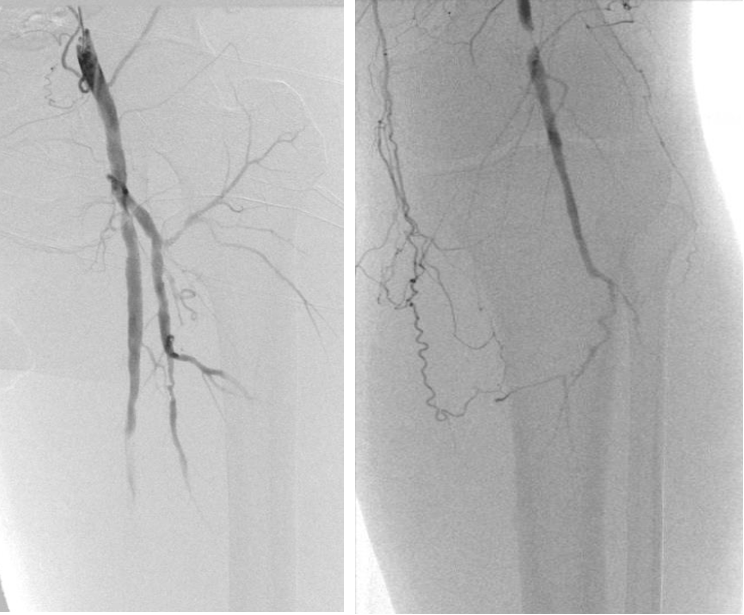

直播病例分析

男性,78岁

左侧下肢间歇性跛行,R3,DM,肌酐280

DUPLEX:左侧SFA起始PSV 360cm/s ;中段320cm/s;P2 380cm/s;膝下动脉闭塞

病变位置 / 严重钙化

旋切后球囊扩张:

股浅动脉DCB 5.5-100;股深动脉 5-20 POBA

腘动脉DCB 5-40

膝下动脉POBA 3-150

病变位置和严重钙化旋切后的处理方法,包括使用DCB和POBA进行球囊扩张。

术前

术后